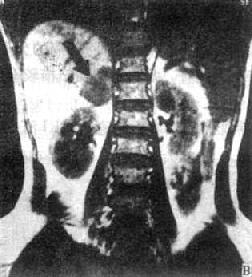

(二)肾上腺皮质腺瘤 肾上腺皮质腺瘤CT可见边缘光滑、圆形或椭圆形肿瘤,密度均匀,等于或低于肾的密度。增强扫描有均一强化。对侧肾上腺萎缩变小,但也可正常。肾上腺皮质瘤因分泌的激素性质不同,而有原发性醛固酮增多症和皮质醇增多症之分。前者腺瘤较小。约0.5~0.3cm。后者腺瘤较大,约2~8cm。均表现为圆形或椭圆形肿块。前者因瘤体小,常仅累及肾上腺的某一部分。两种功能性异常除腺瘤外也可因相应的肾上腺皮质增生所致。MRI腺瘤在T1和T2WI上信号强度与肝的信号相似或稍低于肝(图4-4-9)。

冠状面

图4-4-9 右肾上腺腺瘤MRI(T1WI)